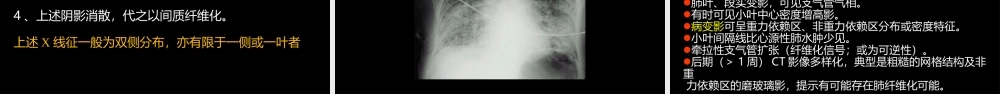

急性呼吸窘迫综合征(AcuteRespiratoryDistressSyndrome)影像学中国石油中心医院影像科杨景震成人呼吸窘迫综合征(AdultRespiratoryDistressSyndrome,ARDS)ARDS,不是一个独立的呼吸系统疾病。它是一种继发于机体严重损伤时出现的以急性、进行性、缺氧性呼吸窘迫(困难)及顽固性低氧血症为临床特征的综合征,是急性呼吸衰竭的一种类型。与急性呼吸窘迫综合征(AcuteRespiratoryDistressSyndrome,ARDS)此综合征曾被称为成人透明膜肺、休克肺、创伤肺、肺毛细血管渗透综合征等。以上命名均有局限,不能反映该综合征本质及重要临床特征。ARDS不仅发生于成人,也见于儿童。ARDS的概念演变第一次世界大战1914-1918创伤相关性大片肺不张第二次世界大战1939-1945创伤性湿肺越南战争1961-1975休克肺1967Ashbaugh首先报道AcuteRespiratoryDistressSyndromeinadult1971Petty正式称为AdultRespiratoryDistressSyndrome,ARDS1992美国胸科协会提出将此征命名为AcuteRespiratoryDistressSyndrome,ARDS1994欧美ARDS会议AcuteLungInjury(ALI.急性肺损伤)ARDS=严重的ALIAdult→Acute(同时发生于小孩)2000年美国心肺与血液研究院(NHBLI)的ARDSnet多中心系列研究2011年10月德国柏林欧洲重症医学年会Ranieri教授提出ARDS新的诊断标准-柏林标准ARDS病因、病理、发病机制•严重肺部感染•胃内容物吸入•肺挫伤•吸入有毒气体•淹溺•氧中毒•严重感染•严重的非胸部创伤•急性重症胰腺炎•大量输血•体外循环•弥漫性血管内凝血间接肺损伤因素直接肺损伤因素直接肺损伤因素病因ARDS发病机制比较复杂,目前仍在研究之中较统一的认识:为各种病因直接或通过炎症反应→毛细血管内皮细胞和肺泡壁Ⅱ型上皮细胞。毛细血管内皮细胞受损,血管通透性增高→水及大分子蛋白漏出、转移到血管外→高渗性间质及肺泡性肺水肿。发病机制及病理肺泡Ⅱ型细胞受损→肺泡表面活性物质合成障碍→肺泡表面张力增高→肺收缩、萎陷、顺应性减低、加重肺水肿。上述改变的后果:严重影响血氧交换→血氧分压顽固性下降→全身缺氧。炎症反应是导致毛细血管内皮及肺泡壁Ⅱ型细胞损伤的主要原因。而炎症反应是通过炎细胞(多核白细胞、单核细胞、巨噬细胞)及体液(细胞因子、脂类介质、氧自由基、蛋白酶补体、凝血和纤溶系统)发生作用。ARDS是因上述多种因素在多个环节发生作用的结果。肺泡表面张力(Surfacetension):在肺泡上皮内表面分布的极薄的液体层,与...